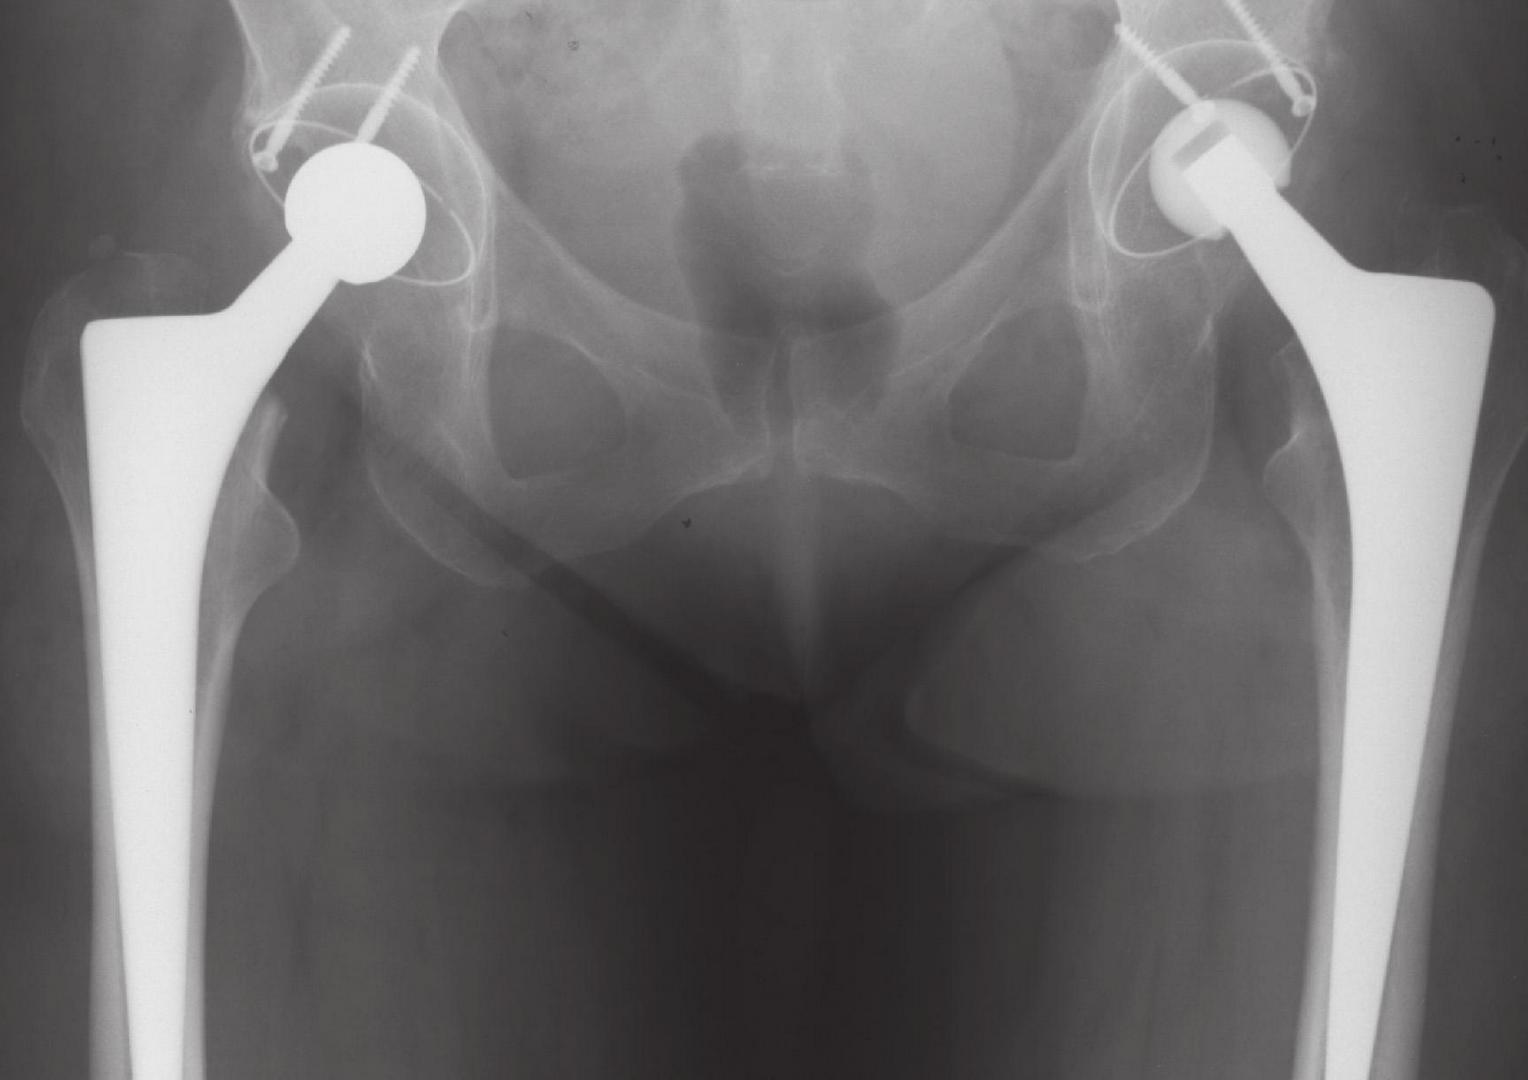

Полное или тотальное протезирование тазобедренного сустава

При этом виде оперативного вмешательства удаляется головка бедренной кости, вместо которой устанавливается два имплантата: искусственная суставная головка, а также искусственный аналог вертлужной впадины. Материалы, из которых изготавливаются суставные протезы, отвечают самым высоким требованиям, что обеспечивает длительное свободное и безболезненное функционирование искусственного сустава. В центре эндопротезирования в Берлине применяются наиболее надежные и хорошо зарекомендовавшие себя в международной практике имплантаты тазобедренного и коленного суставов, прошедшие научно-клинические испытания и удовлетворяющие самым высоким требованиям.